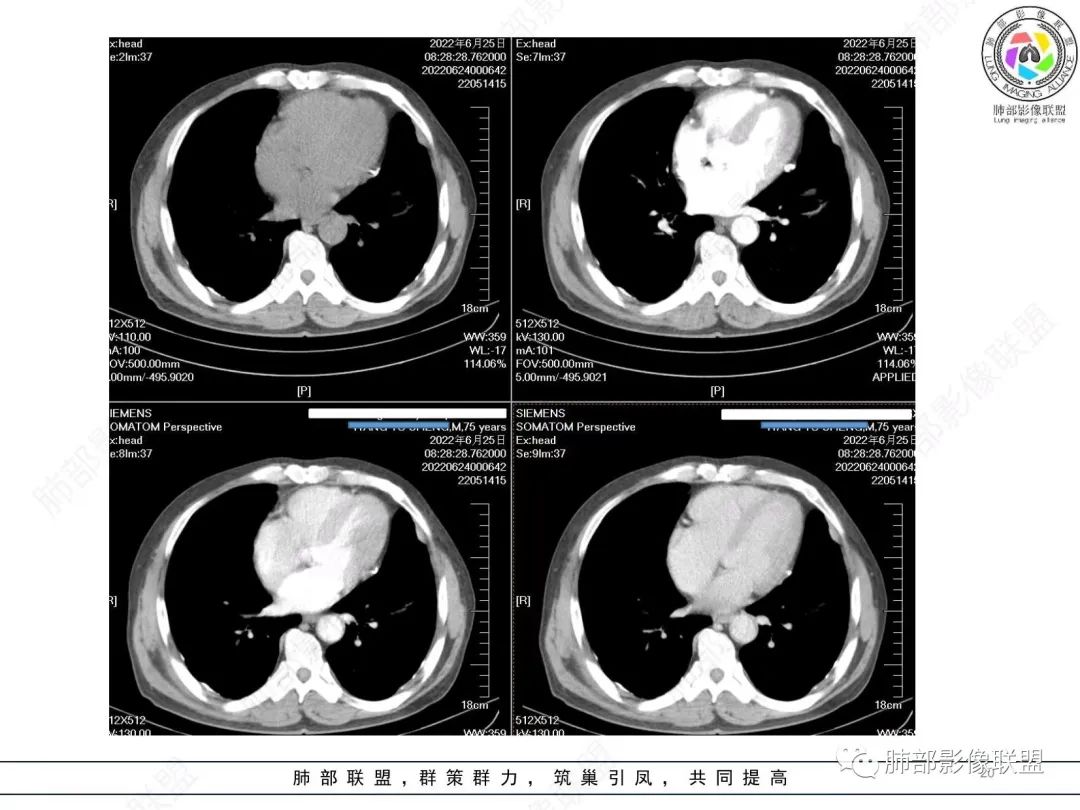

淋巴瘤肯定不符合了。

仅仅只有血管漂浮和支扩支持淋巴瘤。其他细节都是否定淋巴瘤的。

南边:

大肿块、表面光滑但深分叶,肺门侧支气管堵塞

我一开始诊断恶性,定在淋巴瘤,还觉得信心满满

回头看,内部支气管近端其实不连续,伴随肺动脉不存在

这两点就不符合

还有如果从支气管的特点考虑黏膜相关性淋巴瘤,其整体应该是边缘不清楚为主,肺炎样为主。